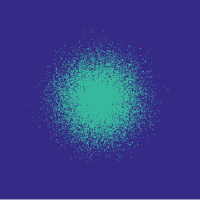

![]() |

Figure 6 (Left) illustrates that the learning-based approach outperforms the randomized variable-density approach. Note that here we use the function with , as introduced in Section II-D. We use Hadamard sampling, since it is easy to implement in digital hardware [28]. The density function of [3] is parametrized by the radius of fully sampled region, , and the polynomial degree, . We choose the parameters’ values that yield the lowest reconstruction error on the training set for each compression rate in the ranges and , taking the best realization over 20 random draws in each case.

Figure 6 (Left) shows example reconstructions at and compressions. A likely reason for the reduced error due to our approach is that we do not assume any shape for the distribution of the indices.